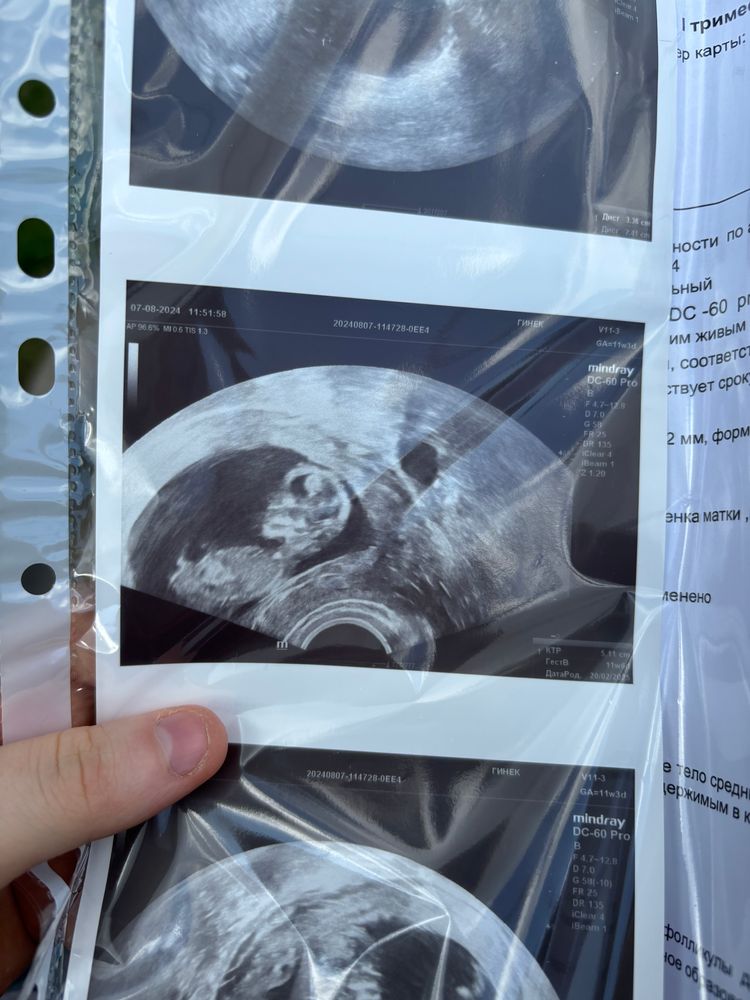

Девочка, только потому что мальчика тут не видно(да и девочки впрочем тоже😄). Вообще не видно полового бугорка.

Я за мальчика , на первом фото

У меня мальчик был отчетливо виден, а у девочки ничего не было видно до 20 недель, поэтому у вас я бы сказала что девочка

Пол на первом скрининге Пол ребёнка